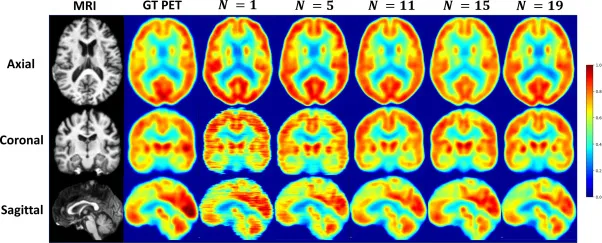

图8.输入邻近切片数量N的消融研究。我们展示了在三种方向(轴位、冠状位和矢状位)上,不同N值下合成的PET扫描图,其中轴位切片作为网络的输入。